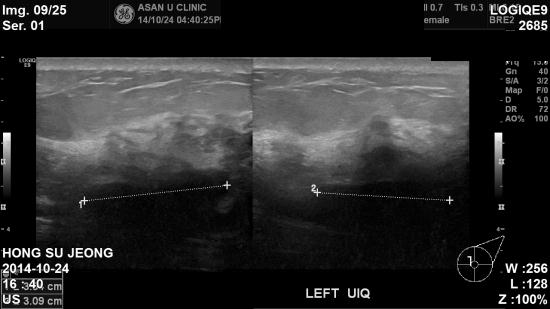

초음파상 좌측 11시방향 0.82cm, 10시 방향 3.34cm 미

좌측 겨드랑이 림프절 비대소견으로

조직검사 및 세침검사 시행 하여

침윤성 유관암 및 겨드랑이 전이로 진단 되었습니다.